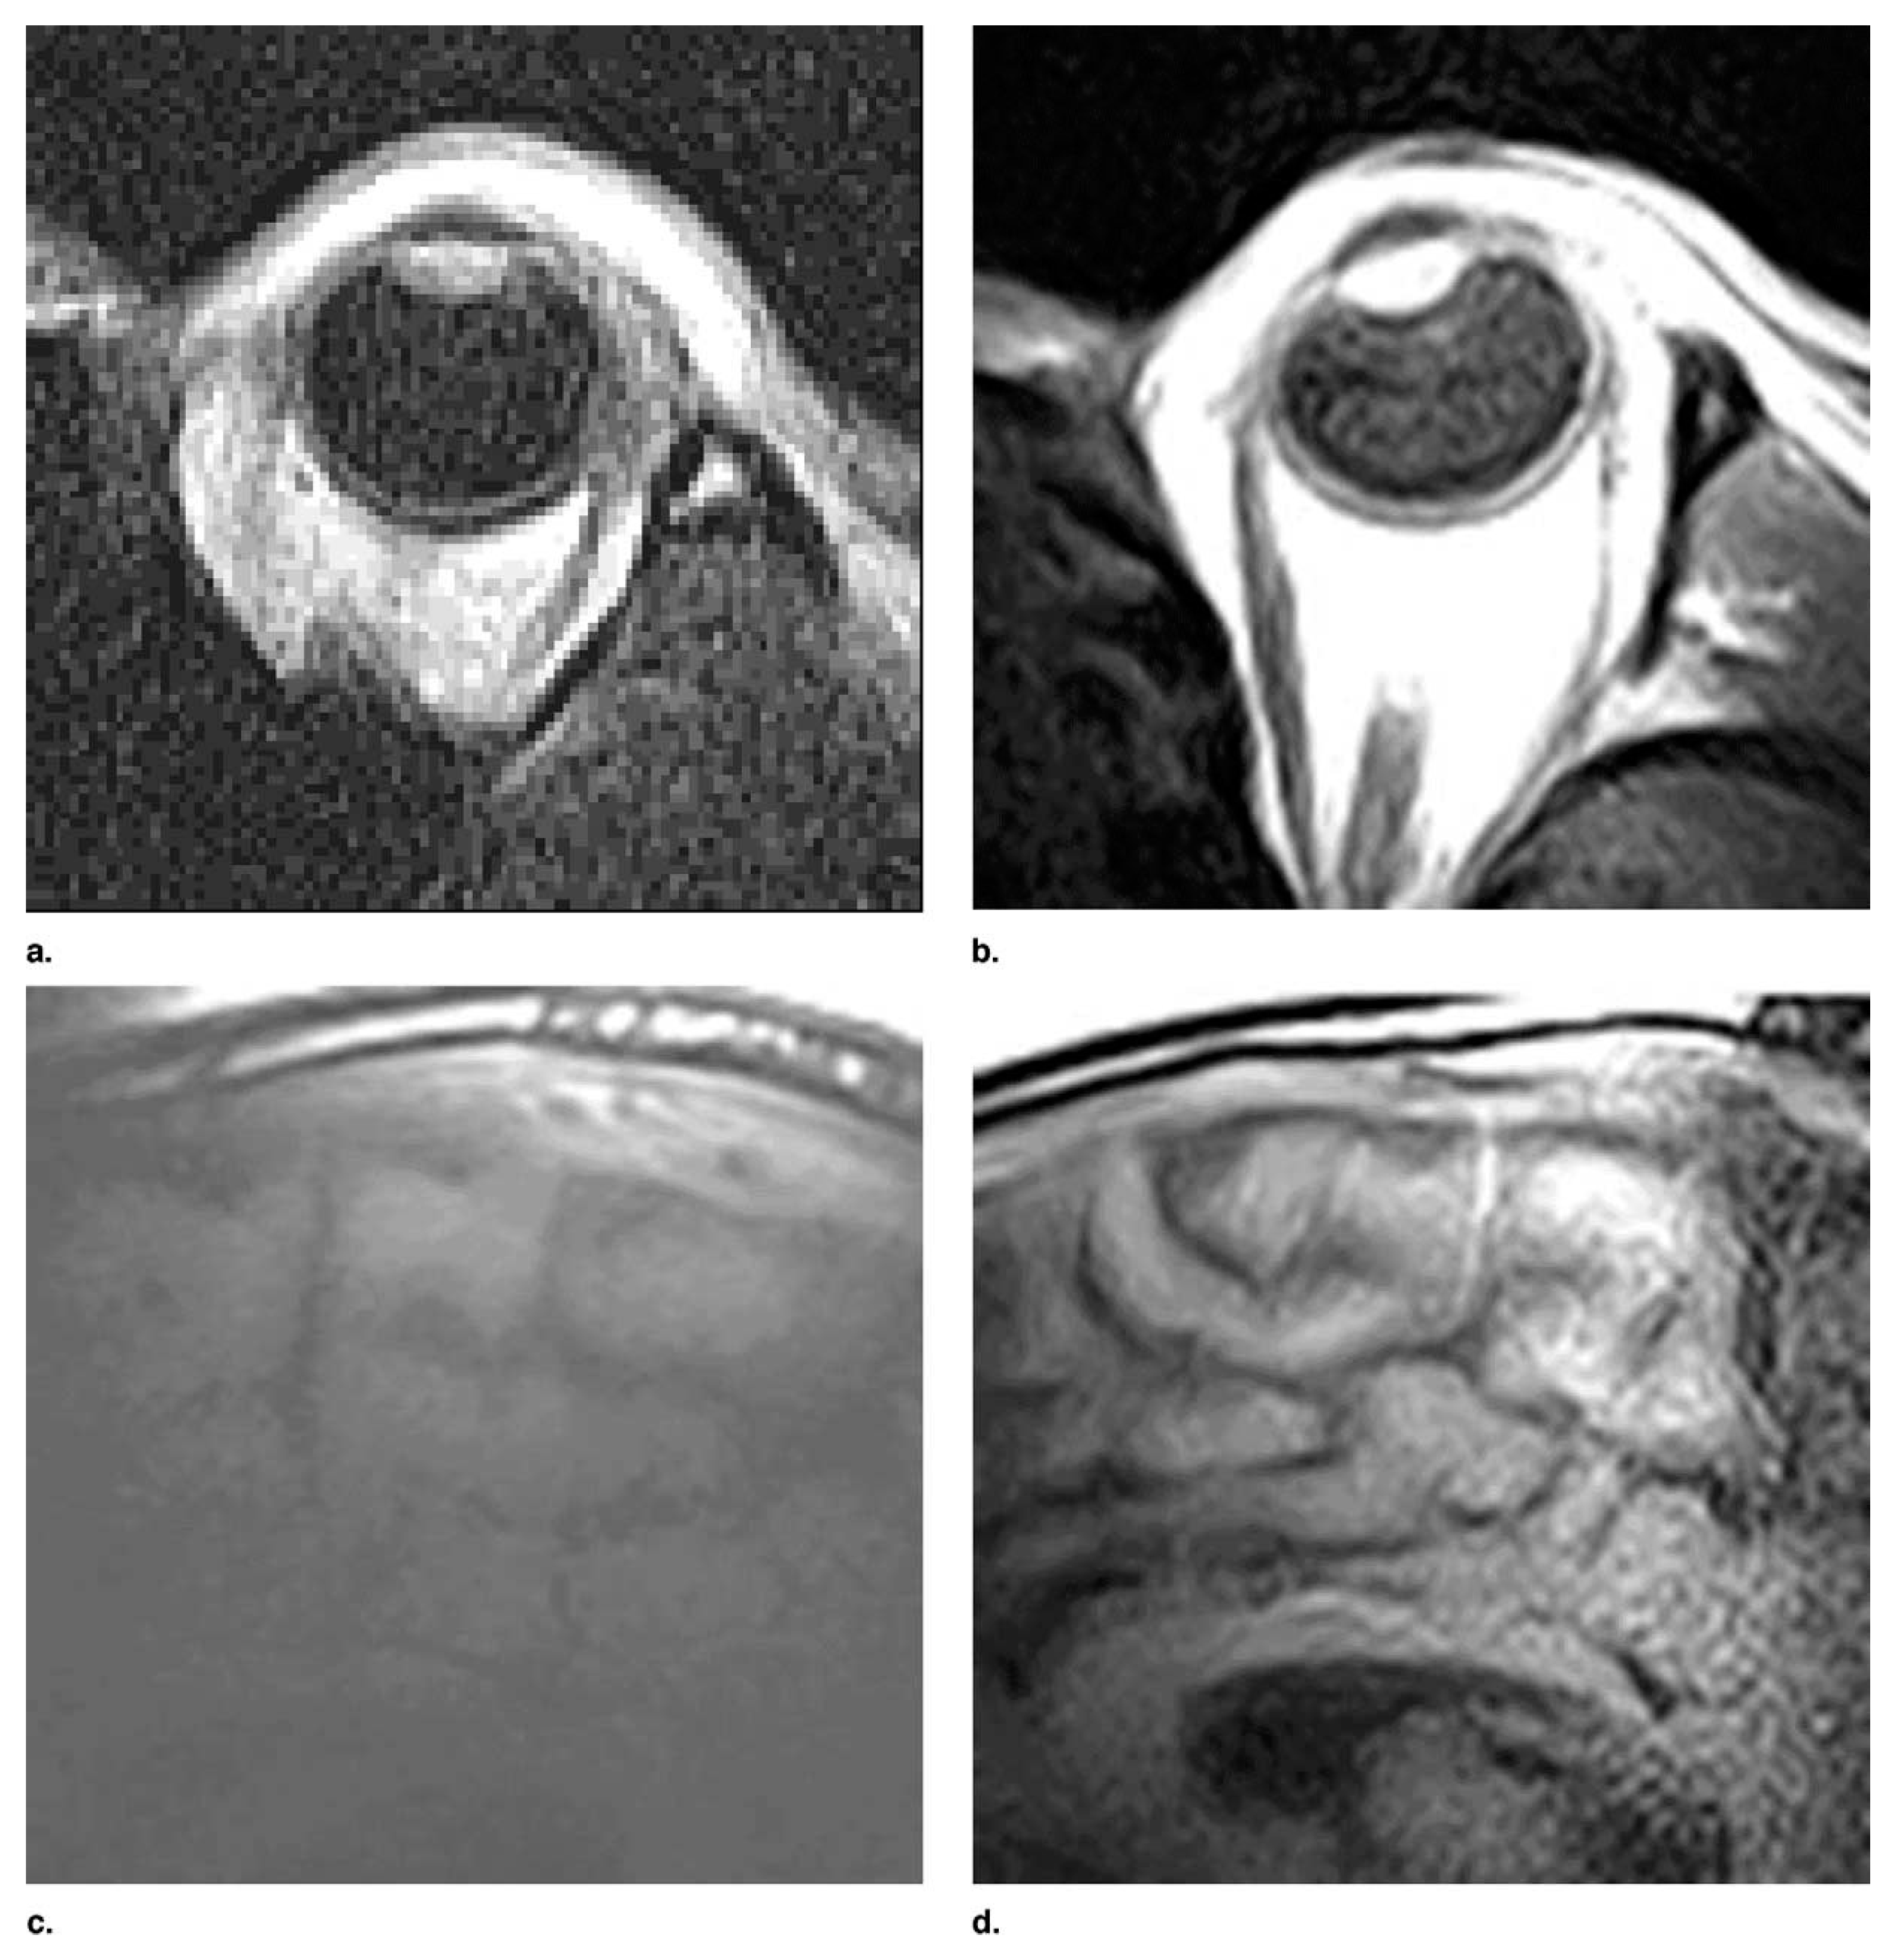

- Giovannetti, G.; Frijia, F.; Flori, A. Radiofrequency Coils for Low-Field (0.18–0.55 T) Magnetic Resonance Scanners: Experience from a Research Lab–Manufacturing Companies Cooperation. Electronics 2022, 11, 4233. [Google Scholar] [CrossRef]

- Wang, B.; Siddiq, S.S.; Walczyk, J.; Bruno, M.; Khodarahmi, I.; Brinkmann, I.M.; Rehner, R.; Lakshmanan, K.; Fritz, J.; Brown, R. A Flexible MRI Coil Based on a Cable Conductor and Applied to Knee Imaging. Sci. Rep. 2022, 12, 15010. [Google Scholar] [CrossRef]